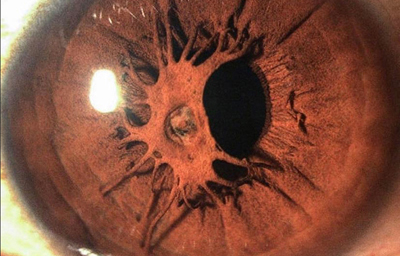

La Atrofia Esencial del Iris. Se produce cuando el endotelio anormal prolifera sobre la superficie del Iris, con subsecuente formación de una membrana contráctil que produce corectopia, atrofia del Iris y policoria falsa; si el endotelio anormal prolifera sobre el ángulo de la cámara anterior genera sinequias y glaucoma.

Atrofia Esencial del Iris - OD de paciente femenina de 36 años

Archivo fotográfico Dr. Carmen Barraquer